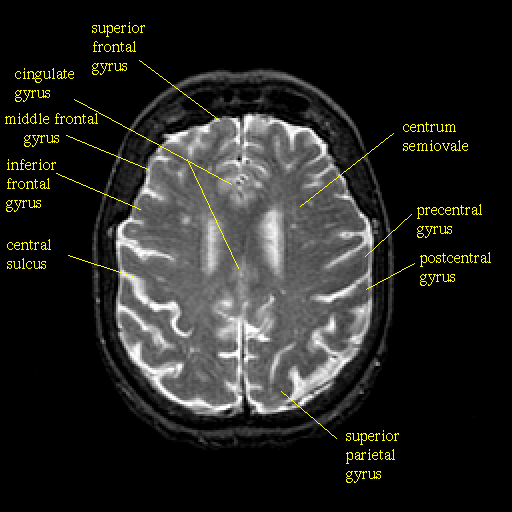

T2-weighted structural MR: Slice 36

Slice 36